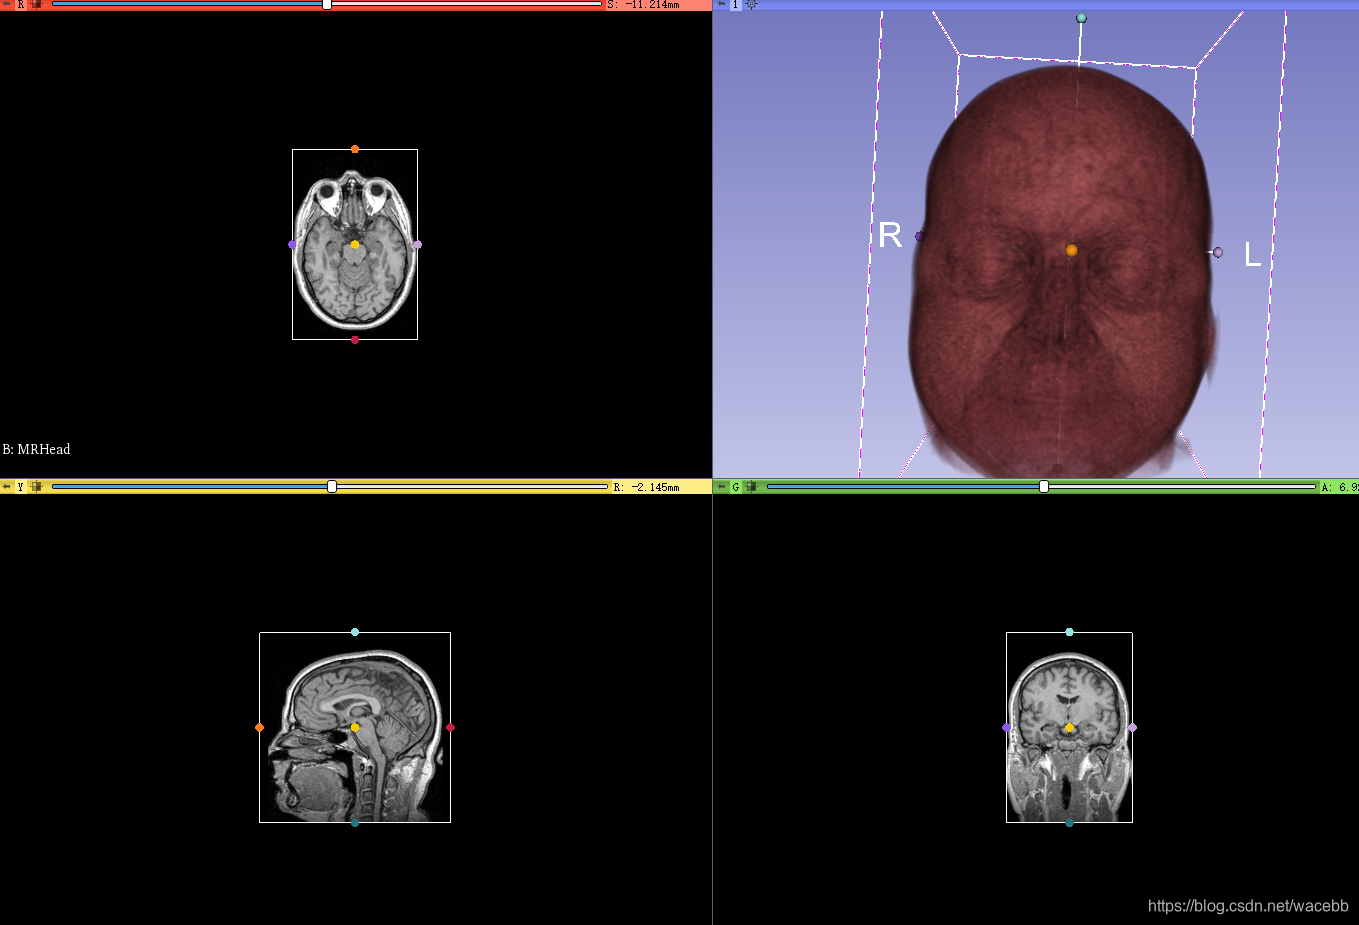

然后

勾选enable 键和眼睛,

就可以进行剪裁了。

于此同时右边显示界面会展示出ROI框:

然后,我们通过移动ROI点就可以修改ROI区域,同时3D显示出ROI区域:

到目前为止,我们只是绘制出了ROI区域,在左边input里可以看到当roi区域的名称,同时下拉菜单可以修改名称:

然后,我们可以选择crop volume,于此同时界面也发生变化:

我们可以看到输入的volume 和 ROI:

然后我们点击下面的apply或者crop按键(版本不一样),

就可以创建好新的ROI,并且在右边显示:

于此同时,我们可以看到文件名称:

这样我们就创建了一个新文件:

我们可以看到input 从一个文件变成了现在的两个: